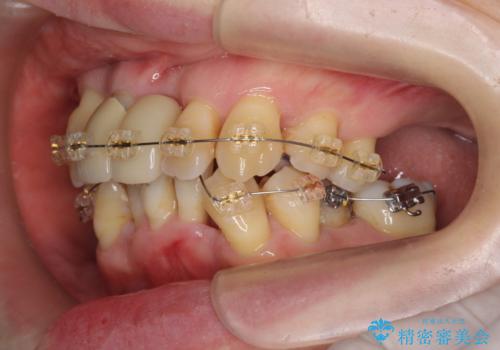

- 重度の歯周病に罹患しており、他院で「多数の歯を抜歯したのち、入れ歯を入れるしかない。」と言われ、入れ歯以外の方法がないか相談のため来院されました。

重度の歯周病で多数の歯を残せない問題、歯並び・噛み合わせの問題、欠損の問題、と多数の大きな問題が認められました。

このままの歯並びでは仮にインプラントを埋入したとしても歯ブラシがしづらく、また歯周病の問題が再発しやすい、と判断し矯正治療を行ったのちに歯周病治療、インプラント治療を行っていく治療計画としました。

インプラント治療に加え、歯周病に対しての再生治療や歯周ポケットの除去を行う歯周外科、矯正治療、と必要な治療は多岐に渡りましたが、最終的に安定した噛み合わせを得られたとともに、清掃のしやすい口腔内環境を確立できました。